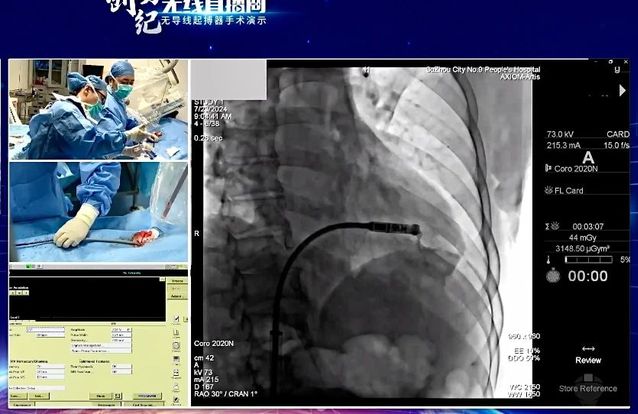

7月24日,“创势纪·无线直播间—苏皖区域无导线起搏器手术演示”在线上举行,亚洲色吧 心血管内科主任吴雁鸣参与手术演示,助力提升区域心血管病防治水平。本次活动由江苏省医学会心血管病学分会副主任委员、苏州市心血管病学分会主任委员、苏州大学附属第一医院心内科主任蒋廷波主持,汇聚了一大批专家教授开展手术演示和线上探讨,通过学术交流积极推动苏皖地区心血管病防治水平的进一步提高。

无导线起搏器,代表心脏起搏领域**技术。无导线起搏器(Micra),俗称胶囊起搏器,是目前世界上最小最轻的起搏器,直径6.7mm,长度25.9mm,重量仅1.75g,是国际前沿的先进起搏技术。虽然小,但其电池续航能力强,工作寿命长达12年,植入后还可以接受1.5T/3.0T核磁共振检查。患者无切口、无伤疤、无凸起、无束缚,几乎感觉不到它的存在,是看不见的起搏器,就像默默守护心律失常患者心脏健康的“隐性保镖”。

这一技术的成熟推广,对区域患者健康有着重要意义。植入心脏起搏器主要针对严重缓慢性心律失常的患者。传统的心脏永久起搏器由脉冲发生器和电极导线组成,医生通过腋静脉或锁骨下静脉将起搏器电极导线送至右心房或右心室,在患者胸前区胸大肌处制作与起搏器大小合适的囊袋,以容纳脉冲发生器。无导线起搏器不同于传统起搏器的地方在于:它不需要使用导线将脉冲发生器连接到起搏电极上。相反,它将脉冲发生器和起搏电极集成在一起,以微缩胶囊的形式直接植入患者的心腔内部。